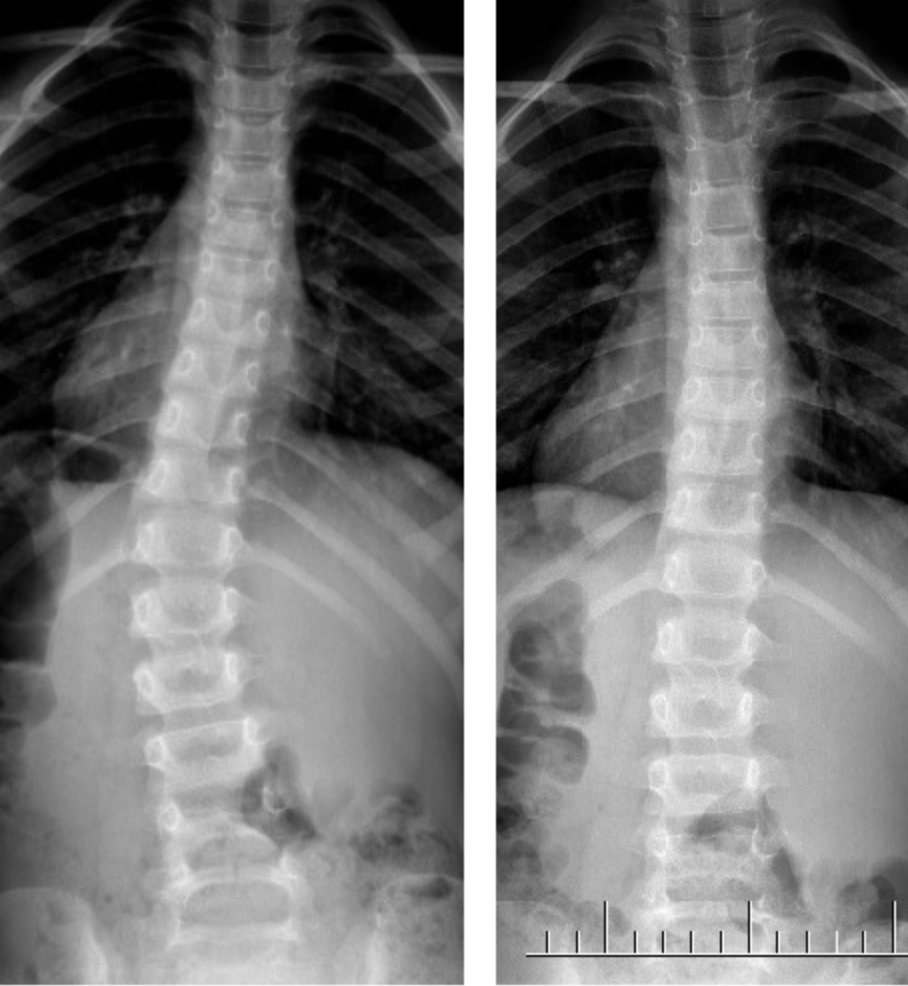

Maciej – 7 lat

Skolioza jednołukowa (statyczna) – zdj. z lewej. Korekcja uzyskana w trakcie jednej wizyty – zdj. z prawej

Dawid – 7 lat